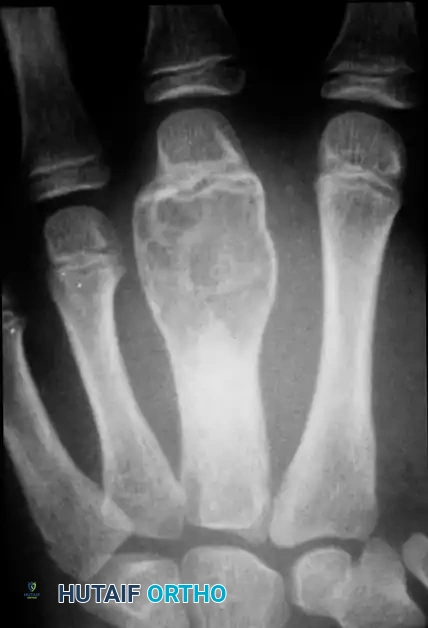

Giant Cell Tumor of the Tendon Sheath (Xanthoma)

Giant cell tumors of the tendon sheath (GCTTS) are the second most common solid cellular tumors of the hand. They occur most frequently between the ages of 8 and 80 years and exhibit a strong predilection for the palmar aspect of the digits. Multiple xanthomas may be indicative of underlying hypercholesterolemia.

Clinical and Histological Profile

GCTTS are typically slow-growing, painless masses. However, when located adjacent to a joint (most commonly the proximal interphalangeal joint), they can mechanically block flexion or extension. Grossly, they appear as yellow or tan lobulated masses. Histologically, they are composed of spindle cells, fibrous tissue, cholesterol-laden histiocytes, multinucleated giant cells, and hemosiderin deposits.

Surgical Excision and Recurrence

Excision is notoriously difficult. These tumors frequently wind in and around the flexor tendons, their synovial sheaths, digital nerves, and occasionally the extensor mechanism, sometimes encompassing three-fourths of

Associated Surgical & Radiographic Imaging

Hutaifortho's Orthopaedic Diagram